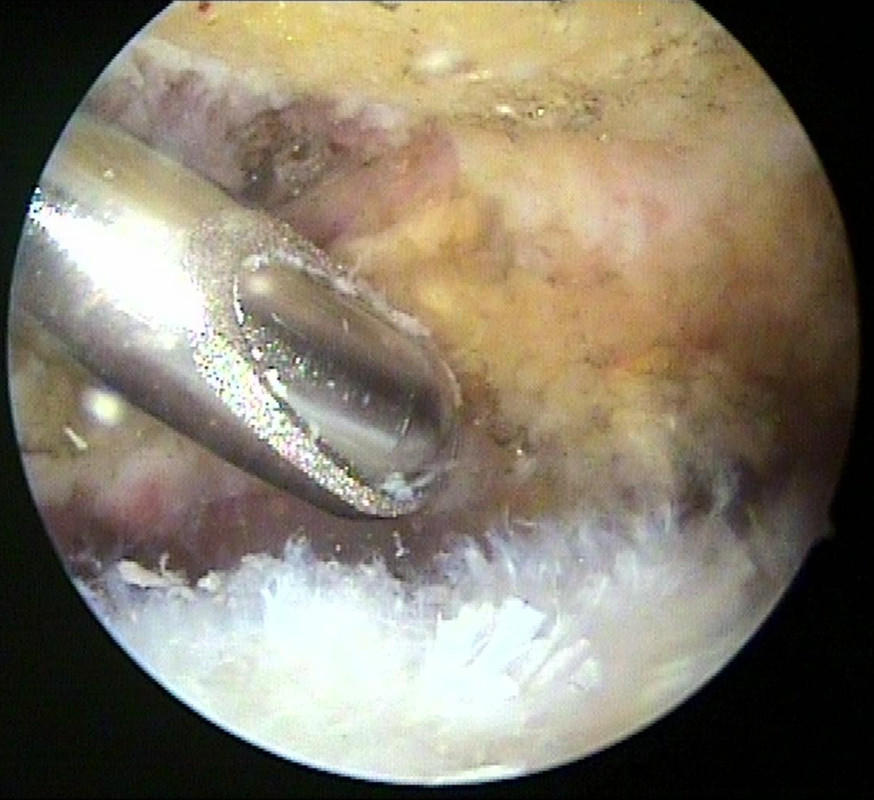

Während der Arthroskopie wird die ganze Schulter von innen untersucht und Knorpel, Sehnen, Schleimhaut, Bänder und eben auch der Knochensporn dargestellt. Der Knochensporn liegt nicht direkt in der Schulter, sondern über der Rotatorenmanschette. Um Ihn gut zu sehen muss meistens vorher der entzündete Schleimbeutel entfernt werden.

Das Bild links zeigt den nach unter ragenden Knochensporn, das Bild rechts zeigt die unter dem Knochensporn aufgeriebene Sehne und ein Operationsinstrument). Dieser Knochensporn wird dann zunächst von den Weichgeweben befreit und mit dann abgetragen, damit die Unterfläche des Schulterdaches dann glatt und eben ist.

Das linke Bild zeigt den „Shaver“ beim Antragen des Knochensporns. Auf dem rechten Bild ist der Knochensporn nun abgetragen, die Sehnenoberfläche geglättet. Der Raum unter dem Schulterdach ist wieder weit genug)